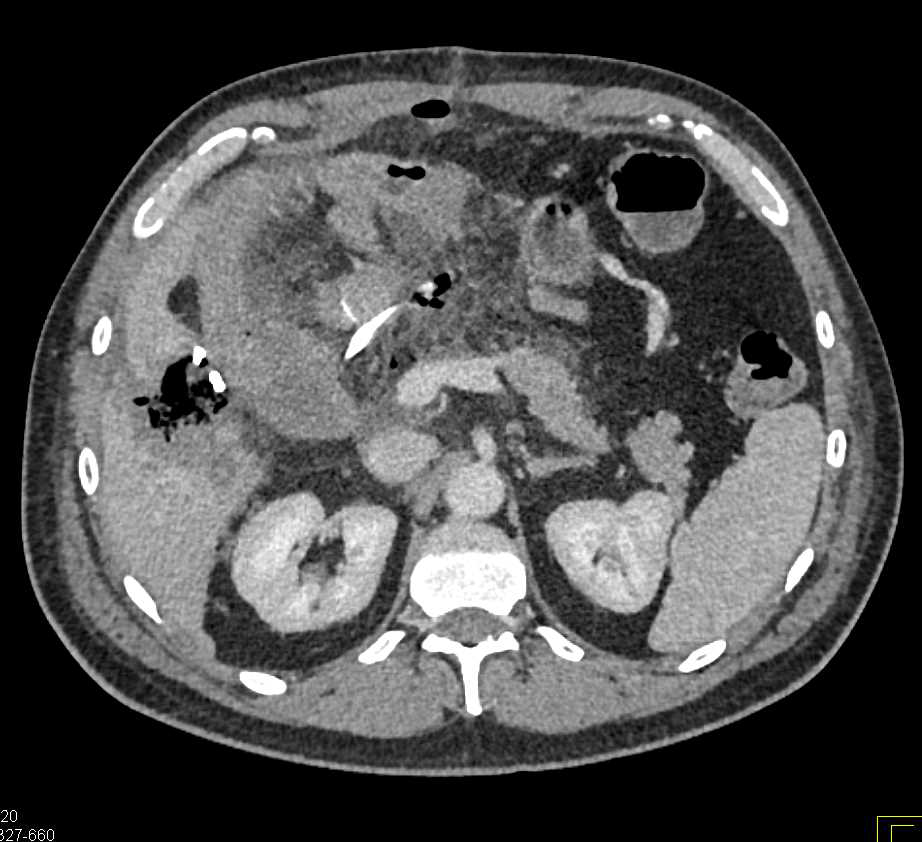

Ampullary Carcinoma Obstructs Common Bile Duct (CBD) and Invades Duodenum